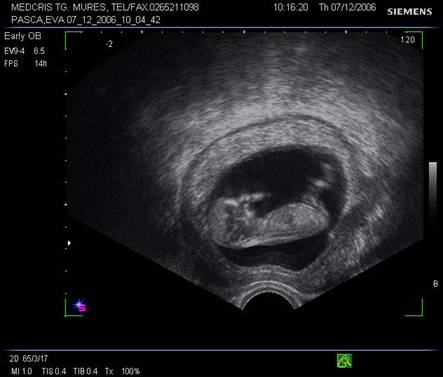

Fig. nr.108. Sarcina 7 saptamani la ecografia abdominala.

Fig. nr.112 Sarcina 12 saptamani la ecografia transvaginala